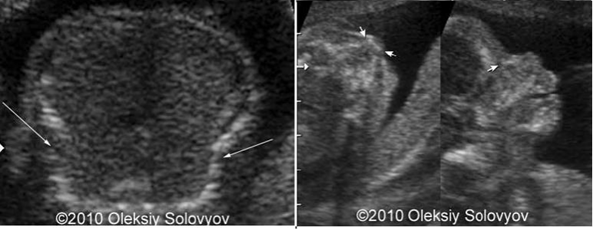

Siêu âm trước sinh có thể chẩn đoán chính xác bệnh đến 89%. Việc chẩn đoán có thể thực hiện sớm nhất ở tuần 17  với typ I và tuần 13 với typ II. Bệnh typ III hoặc IV có thể có hoặc không có gãy xương, biến dạng xương hoặc giảm khoáng hóa xương, nếu có thì sự biến đổi chi nhìn thấy được ở 3 tháng cuối thai kỳ.

Hình ảnh siêu âm thai ở 20 tuần

(Mũi tên cho thấy gãy xương sườn, giảm khoáng ở xương mũi)